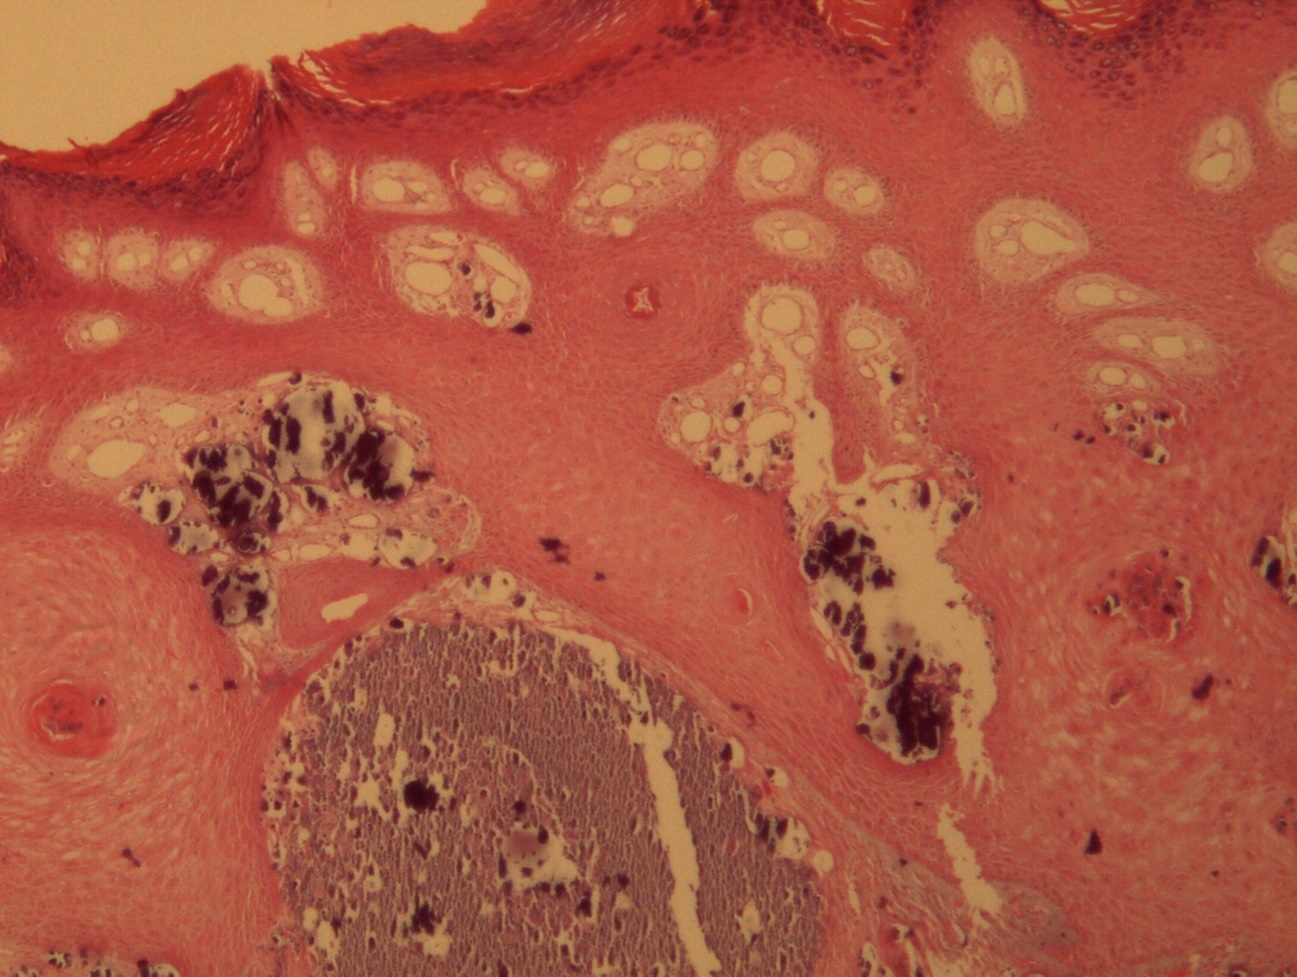

A 9-year-old male patient who was treated in the dermatology service for a progressively growing keratotic nummular dermal lesion on the right knee. With the clinical judgment of viral wart, the lesion was removed. In the Pathology Service, a nummular keratotic lesion of 0.5 cm in maximum dimensions was received, which crackled when cut. Figure 1, Figure 2, Figure 3, Figure 4, Figure 5

Figure 3.Relationship of calcium foci in the papillary dermis with the overlying epidermal hyperplasia. HE. 200x.

Calcinosis cutis refers to the deposit of calcium salts on the skin. It generally constitutes a morphological type of dystrophic calcium deposit, related to different types of lesions or injured tissues (in this case a common wart) without alterations in calcium metabolism in biochemical studies, typical of metastatic calcifications.

The presence of intralesional calcium deposits is not associated with prognostic consequences. In fact, it is a morphological finding that is anecdotal in most cases. However, it can lead to errors in initial clinical judgement. Depending on its extension and location within the lesion (superficial or deep) it can alter its properties.